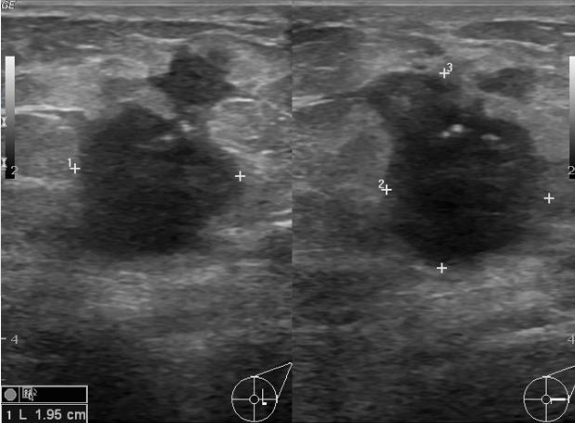

Que tipo de tumor este nódulo sugere?

A

MALIGNO